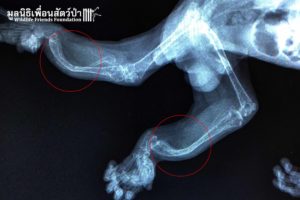

The Veterinary Team did an initial examination and x-ray, they found Tufa has a severe case of metabolic bone disease (MBD) which is commonly found in most vertebrates. MBD is caused by improper nutrition, calcium deficiency, and vitamin D deficiency. In this case, Tufa’s limbs are deformed and in a fragile state which makes it very difficult for him to crawl or climb in a tree the way a slow loris is supposed to.

ทีมสัตวเเพทย์ได้ตรวจร่างกายพร้อมกับ X-ray จึงพบว่า ทูฟาเป็นโรคกระดูกเมตาบอลิกหรือโรคกระดูกพรุนซึ่งสามารถพบได้บ่อยในสัตว์เลื้อยคลานหรือสัตว์ที่มีกระดูกสันหลังทุกชนิด ส่วนใหญ่เกิดจากสัตว์ที่ไม่ได้รับสารอาหาร วิตามิน หรือเเสงเเดดที่เหมาะสม อย่างในเคสนี้ทำให้กระดูกของทูฟาโค้งผิดรูป บางลง เเละอยู่ในสภาพอ่อนเเอ สามารถคลานหรือปีนต้นไม้ได้อย่างลำบาก